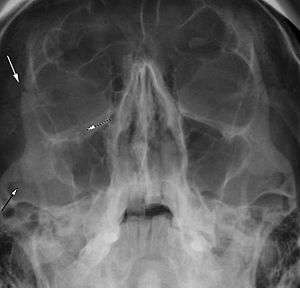

| Right zygomaticomaxillary complex fracture with disruption of the lateral orbital wall, orbital floor, zygomatic arch and maxillary sinus. | |

The zygomaticomaxillary complex fracture, also known as a quadripod fracture, quadramalar fracture, and formerly referred to as a tripod fracture or trimalar fracture, has four components: the lateral orbital wall (at either the zygomaticofrontal suture superiorly along the wall or zygomaticosphenoid suture) inferiorly, separation of the maxilla and zygoma along the anterior maxilla (near the zygomaticomaxillary suture), the zygomatic arch, and the orbital floor near the infraorbital canal.